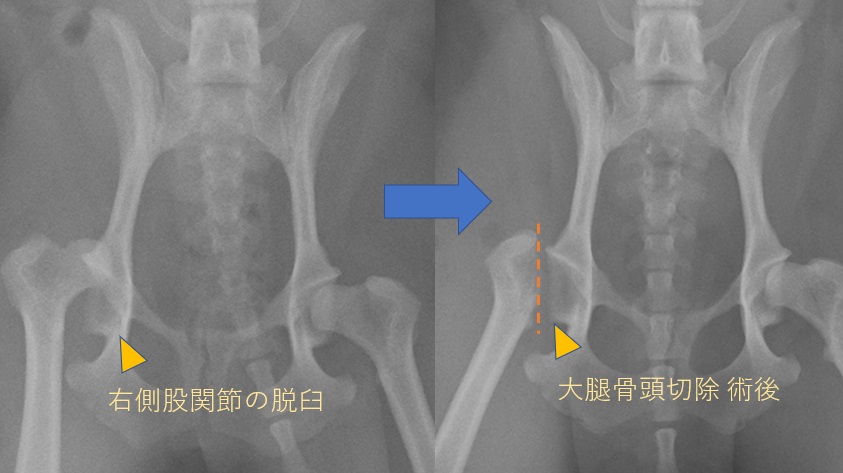

犬の膝蓋骨脱臼整復について - Polaris Vetーポラリスベットー, 股関節脱臼 |ライオン動物病院|三鷹市・調布市の動物病院

股関節脱臼 |ライオン動物病院|三鷹市・調布市の動物病院